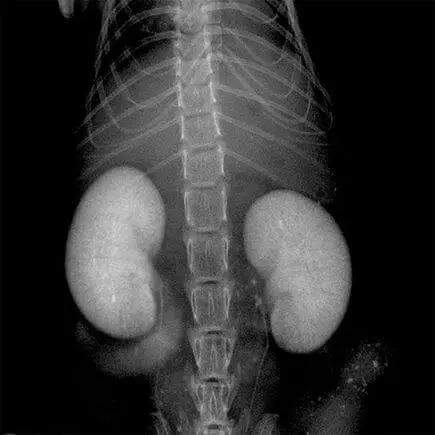

Metastaza nowotworu, znakowanie bioluminescencyjne: IVIS Spectrum CT